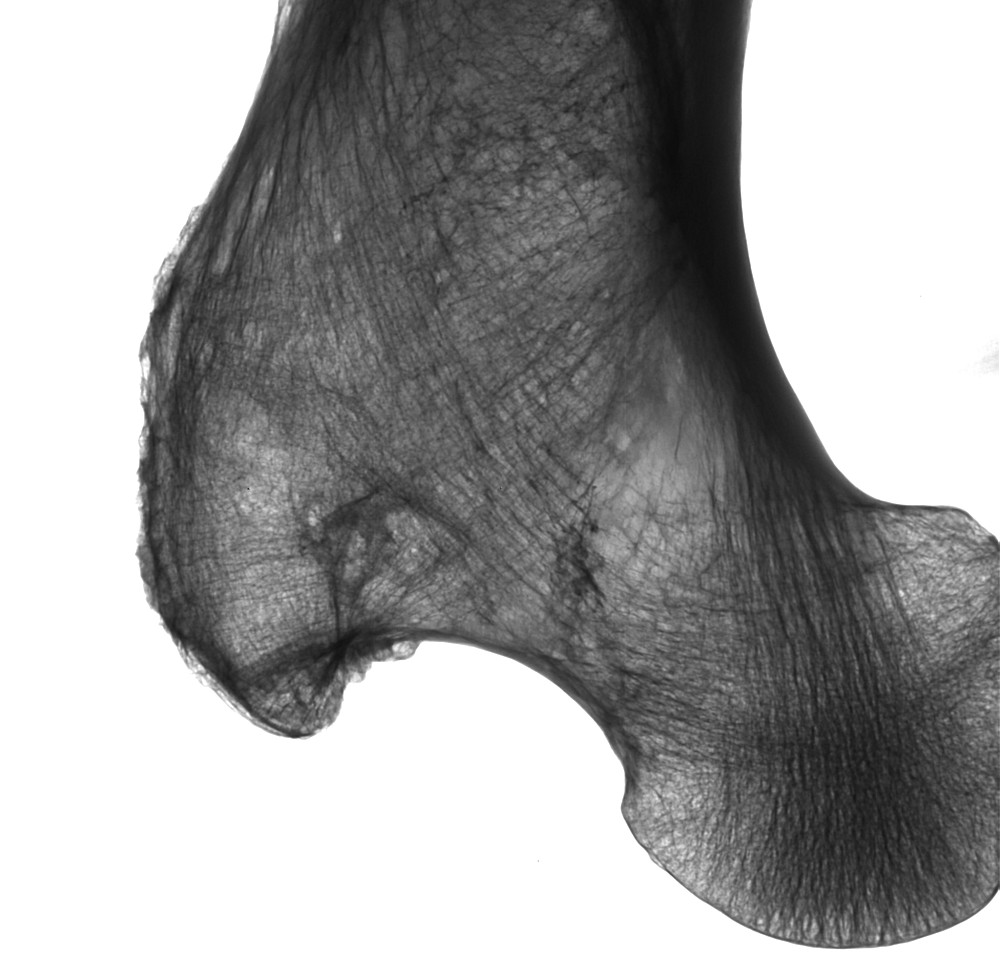

Femur-Knochen (60 kV/0,2mA)